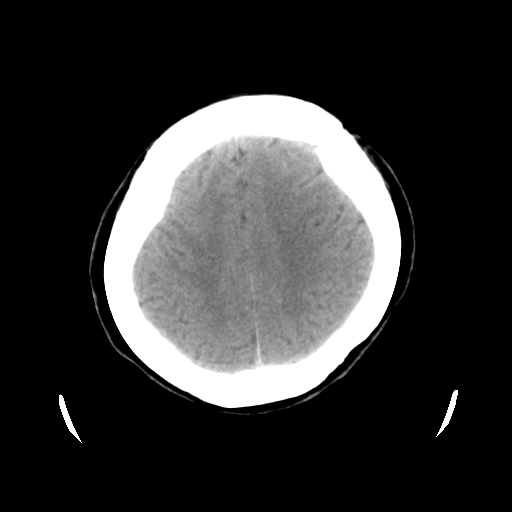

以下是引用cgf在2010-1-3 17:53:00的发言:[br]此病例多考虑:透明隔发育异常 透明隔囊肿可能性大;右侧基底节区(尾状核头)小片状低密度影考虑陈旧性腔梗[br][br]透明隔发育异常:包括透明隔间腔(第五脑室)、韦氏腔(第六脑室)、透明隔囊肿、透明隔缺如;前两者属于正常变异,后两者属于发育畸形;[br]透明隔间腔向下扩张形成韦氏腔;[br]有时透明隔间腔与透明隔囊肿很难鉴别;透明隔间腔间距一般不超过0.5cm,间距大于0.5cm时应考虑透明隔囊肿;[br]透明隔缺如为两侧脑室间隔缺如、融合成单脑室畸形,可伴有智力发育异常;[br][br]

以下是引用liaoqiang在2010-1-3 16:04:00的发言:[br]考虑侧脑室脉络丛囊肿?不除外变异的威氏腔。

以下是引用江广1996在2010-1-3 20:17:00的发言:[br]考虑变异的威氏腔。不除外侧脑室脉络丛囊肿.[br]透明隔囊肿大多数偏前,在侧脑室前角之间。